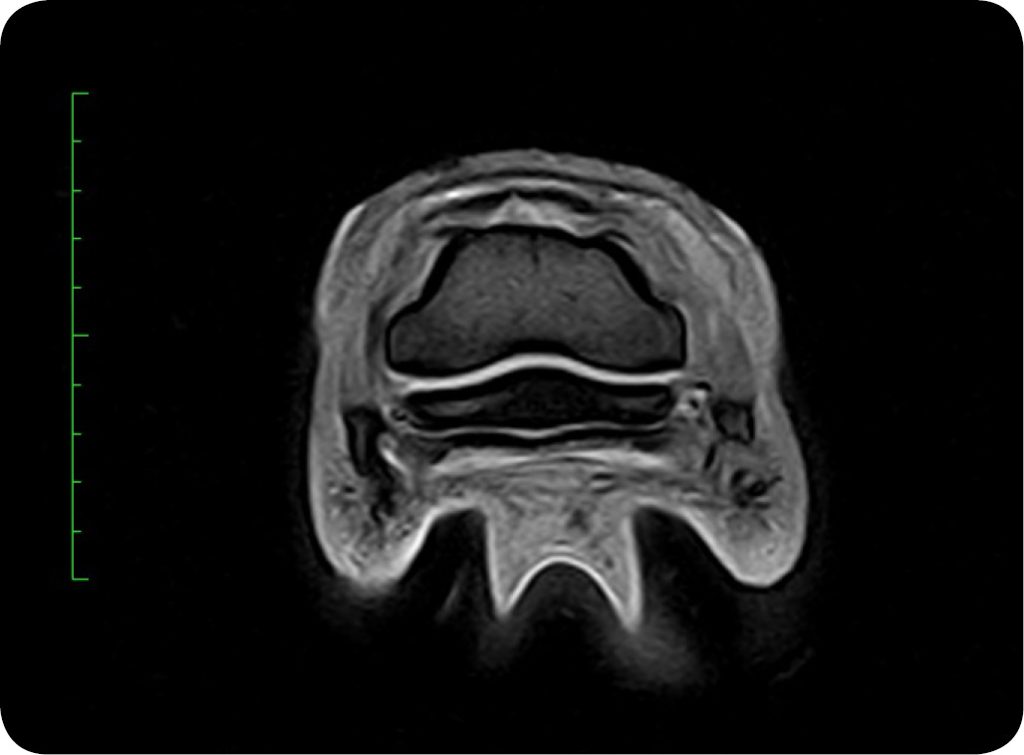

Miejscowe lub uogólnione podwyższenie intensywności sygnału części gąbczastej trzeszczki kopytowej obserwowane było u 64% koni z grupy koni niewykazujących kulawizny (2). Z kolei zmiany, które były wiązane z kulawizną, to pogrubienie i nieregularność warstwy zbitej części dystalnej trzeszczki oraz obniżenie sygnału trzeszczki kopytowej we wszystkich sekwencjach będące konsekwencją mineralizacji kości (ryc. 3). Ubytki części zginaczowej zbitej trzeszczki i chrząstki włóknistej również były wiązane z kulawiznami. Uogólnione podwyższenie intensywności sygnału trzeszczki kopytowej wraz z obniżeniem jego intensywności w obrazach T1-zależnych określane jest mianem wzoru typu obrzęk kości, a histopatologicznie wiąże się z obecnością martwicy kości, włóknieniem, obrzękiem, krwawieniem i przebudową beleczek kostnych (10) (ryc. 3).